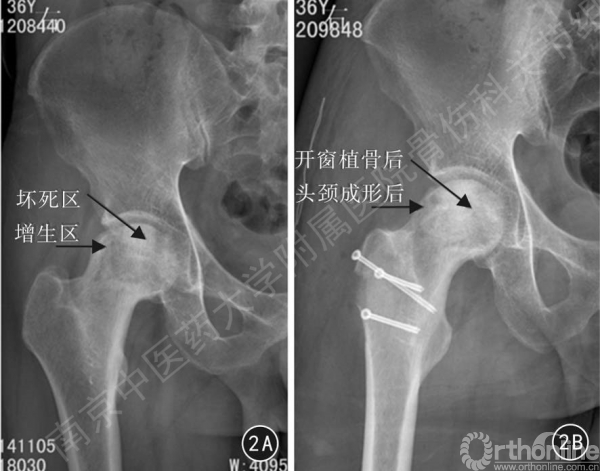

图2 患者男,36 岁,右侧酒精性股骨头无菌性坏死(ⅢA期)合并髋臼头颈撞击综合征,采用髋关节外科脱位死骨清理打压植骨治疗

2A 术前正位X 线片可见股骨头坏死区硬化及囊性变,头颈部异常增生

2B 术后6 个月正位X线片可见股骨头囊变区植骨后外形饱满,强度增强,截骨块愈合